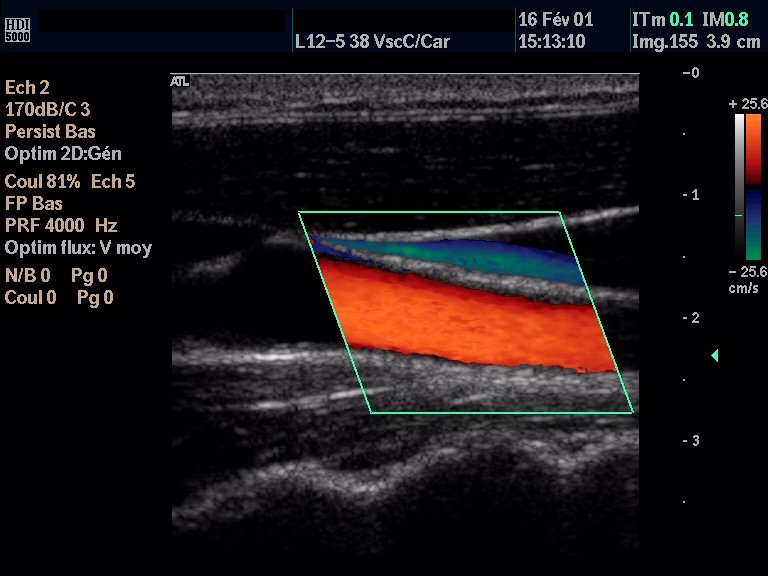

3.4 Exemple d’application à l’Hôpital de Creil

Equipements concernés : les équipements très informatisés :

-automates de laboratoires

-les équipements d’exploration fonctionnelle

-les échographes